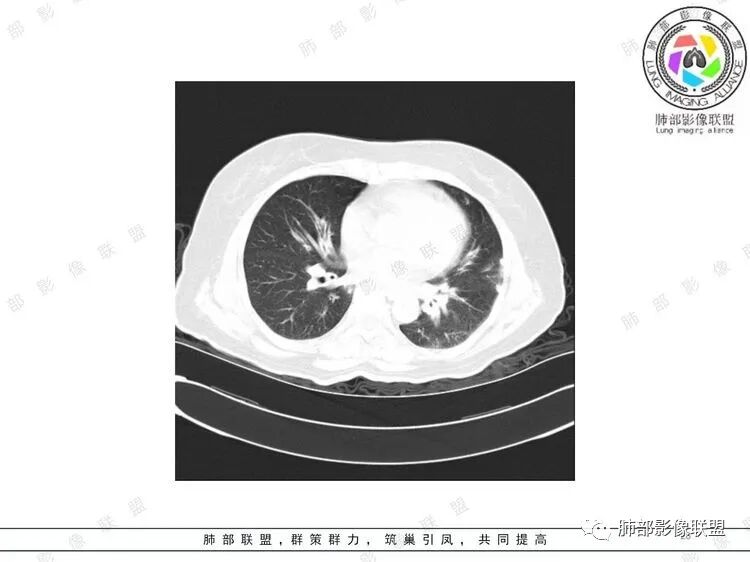

胸CT:双中下肺支气管壁明显增厚,双下肺胸膜下可见实变区。部分病变呈楔形影。

双肺多发大小不等结节,周围伴有晕征,边界模糊,部分结节内似可见支气管影,双肺血管束明显比支气管增粗,临床有感染症状,考虑GPA,疱疹病毒。

双肺支气管管壁弥漫性增厚,管腔狭窄,下叶为主,伴多发高密度结节影,边缘模糊,双肺支气管血管束明显增粗,临床症状咳嗽低热,有血尿,首先考虑血管炎

影像上:多发结节沿血管分布;双下叶支气管血管束简直增厚,偏血管,支气管通畅

因为支气管壁增厚,远端应该小气道病变,这个不是,反而是血管增粗明显

加上结节的分布,支持血管相关病变